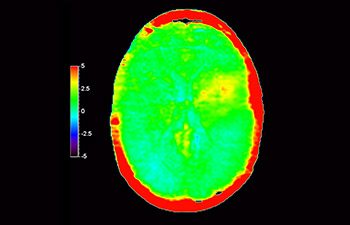

Neurologische Leiden stellen eine schwere Belastung dar. Philips hat es sich zum Ziel gesetzt, hochwertigste Neuro-Bildgebung zu ermöglichen – für eindeutige Diagnosen und eine schnelle Therapie. Wenngleich die MRT heutzutage den Goldstandard in der neuroradiologischen onkologischen Bildgebung darstellt, kann die Genauigkeit beim Tumor-Grading und den Nachsorgeuntersuchungen noch weiter verbessert werden. 3D APT (Amide Proton Transfer) ist eine einzigartige, kontrastmittelfreie Methode zur MR-Tomographie des Gehirns, die den Bedarf nach einer sichereren Diagnose in der Neuroonkologie erfüllt. 3D APT nutzt das Vorhandensein von endogenen zellulären Proteinen zur Erzeugung eines MR-Signals, das direkt mit der Zellproliferation, einem Marker für Tumoraktivität, korreliert. 3D APT kann geschulte medizinische Fachkräfte dabei unterstützen, gering differenzierte von hochdifferenzierten Gliomen und Tumorverhalten von Behandlungseffekt zu unterscheiden1.

mit 3D APT